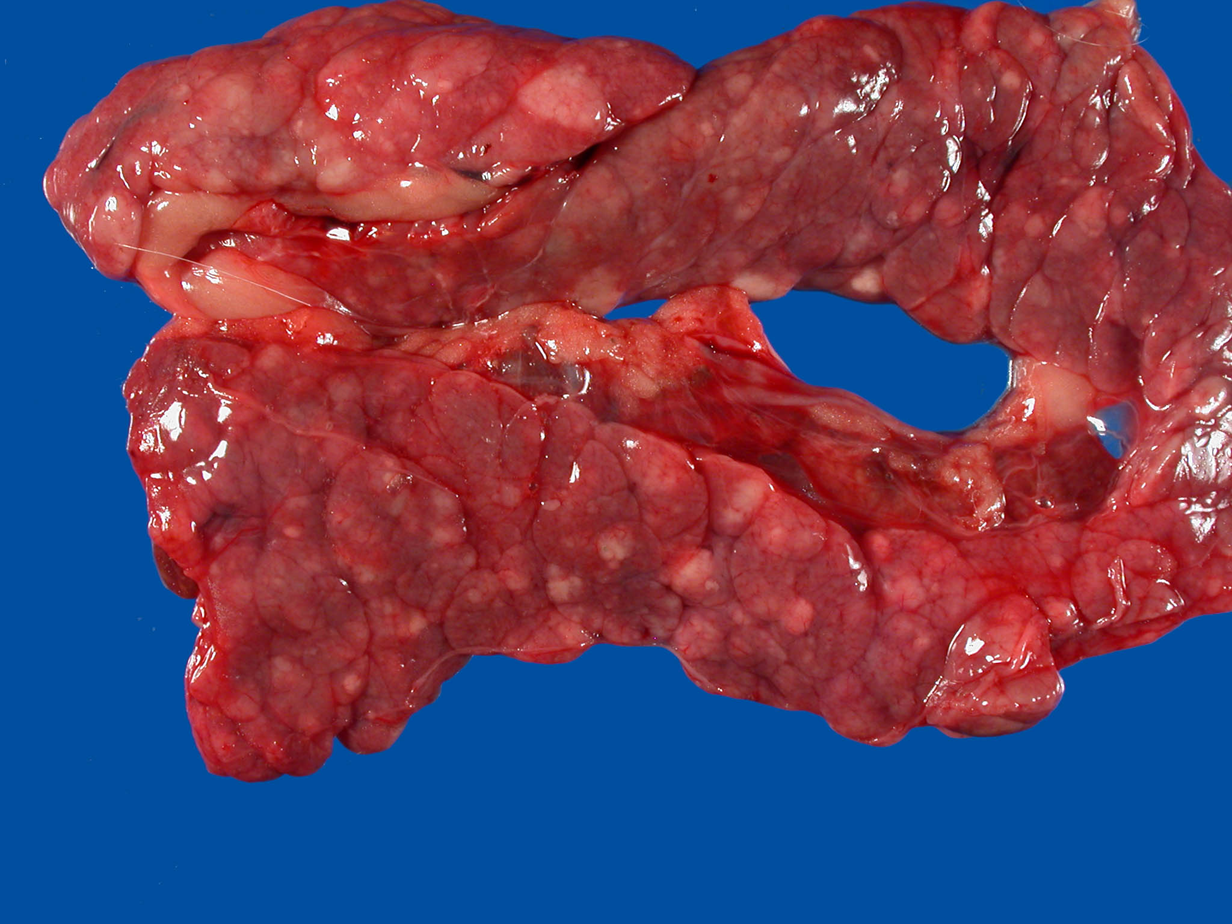

Lungs: congestion

What is this?

Pulmonary edema

Organ -- Lung

Morph. description: Diffusely, left lung lobes are dark red

In the left lung lobes diffusely scattered there are multifocal white to gray, small to pinpoint foci.

Morph. dg.: Lung – necrosis, multifocal, moderate

Etiology -- toxoplasma gondii (protozoal organism)

Disease – toxoplasmosis